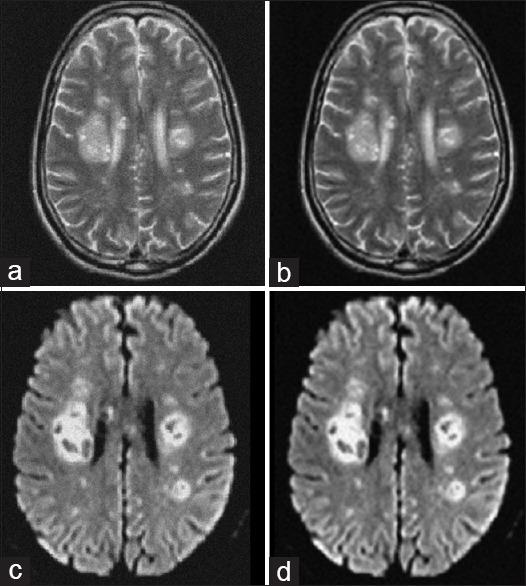

Brain image segmentation can be helpful in the detection of the regions damaged by the effects of coronavirus. Since every image given by photography devices may have noises, therefore, first of all, the brain magnetic resonance angiography (MRA) images must be denoised for best investigation. In the present paper, we have presented the construction of multishearlets based on multiwavelets for the first time and have used them for the purpose of denoising. Multiwavelets have some advantages to wavelets. Therefore, we have used them in the shearlet system to expand the properties of multiwavelets in all directions. After denoising, we have proposed a scheme for the automatic characterization of the initial curve in the active contour model for segmentation. Detecting the initial curve is a challenging task in active contour-based segmentation because detecting an initial curve far from the desired region can lead to unfavorable results.

The results show the performance of using multishearlets in detecting affected regions by COVID-19. Using multishearlets has led to the high value of peak signal-to-noise ratio and Structural similarity index measure in comparison with original shearlets. Original shearlets are constructed from wavelets whereas we have constructed multishearlets from multiwavelets.

The results show that multishearlets can neutralize the effect of noise in MRA images in a good way rather than shearlets. Moreover, the proposed scheme for segmentation can lead to 0.99 accuracy.

脑图像分割有助于检测受冠状病毒影响而受损的区域。由于摄影设备给出的每幅图像可能都有噪声,因此,首先必须对脑磁共振血管造影(MRA)图像进行去噪,以便进行最佳研究。在本文中,我们首次提出了基于多小波的多剪切波构造,并将其用于去噪目的。多小波相对于小波有一些优势。因此,我们在剪切波系统中使用它们,以在各个方向上扩展多小波的特性。去噪后,我们提出了一种在主动轮廓模型中自动表征初始曲线以进行分割的方案。在基于主动轮廓的分割中,检测初始曲线是一项具有挑战性的任务,因为检测到远离期望区域的初始曲线可能会导致不理想的结果。

结果显示了使用多剪切波检测COVID-19感染区域的性能。与原始剪切波相比,使用多剪切波导致了更高的峰值信噪比和结构相似性指数测量值。原始剪切波是从小波构造而来,而我们是从多小波构造多剪切波。

结果表明,多剪切波能够比剪切波更好地消除MRA图像中的噪声影响。此外,所提出的分割方案可实现0.99的准确率。